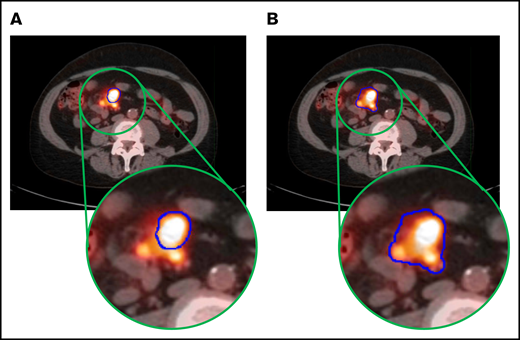

Following 18F-FDG PET/CT scan automatic marking, lesions were edited by a physician (E.A.D.) and confirmed by a radiologist (H.L. or M.S.M.). First, lesions due to physiologic FDG uptake (eg, brain or bladder) and nonmalignant lesions (eg, degenerative disk disease) were removed (MTV semiautomated). Malignant lesions erroneously omitted were then added, and individual lesion contours were adjusted via the paintbrush tools to match tumor boundary precisely (MTV manual). Bone marrow tumor infiltration was included in the calculations. Reactive marrow due to chemical or physical stimulation was excluded. Figure 1 shows an example of tumor lesion manipulation on an 18F-FDG PET/CT scan.

Example of a case of MTV calculations in a patient via the 2 investigated MTV estimation methods. PET images in the MTV semiautomated method (A) and MTV manual method (B), with tumor outlined in blue.

This study establishes the association of MTV on baseline 18F-FDG PET/CT with OS and PFS in patients with refractory/relapsed LBCL treated with axi-cel using 2 separate cohorts of patients. There was lack of agreement between MTV derived by either of 2 different MTV calculation methods, MTV semiautomated and MTV manual, and SPD or SUVmax, which was expected considering the difference in extent and type of measurement. The manually and semiautomated MTV values correlated; however, there was considerable variation in the estimated MTV depending on method. We, a priori, considered the MTV manual method to be superior, as it clearly abrogates the exclusion of some tumor areas using the MTV semiautomated method (Figure 1). Therefore, our model was constructed using MTV manual values.